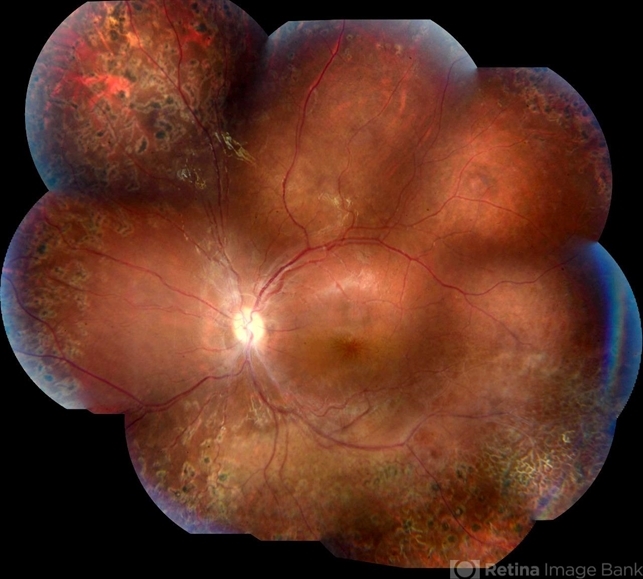

- retinoschisis, Coats' disease

- A 14-year-old male patient was admitted for visual evaluation. Visual acuity s/c in the right eye and 20/80 in the left eye. According to family members, he reported low vision since childhood. He had already undergone treatment with photocoagulation in another service to which he had a diagnostic hypothesis of Coats' disease. Laboratory tests were requested (HIV, TOXO, TOXOCARIASIS, ECA, VDRL, PPD). In the evaluation it was observed important exudation in the posterior pole, some vascular irregularities in the right eye. In the left eye, there is retinoschisis affecting the entire posterior pole and the region nasal to the optic disc, macula with a characteristic aspect of a cartwheel. Well exemplified by OCT-A (Structrure Deep: IPL - 25, OPL - 25).